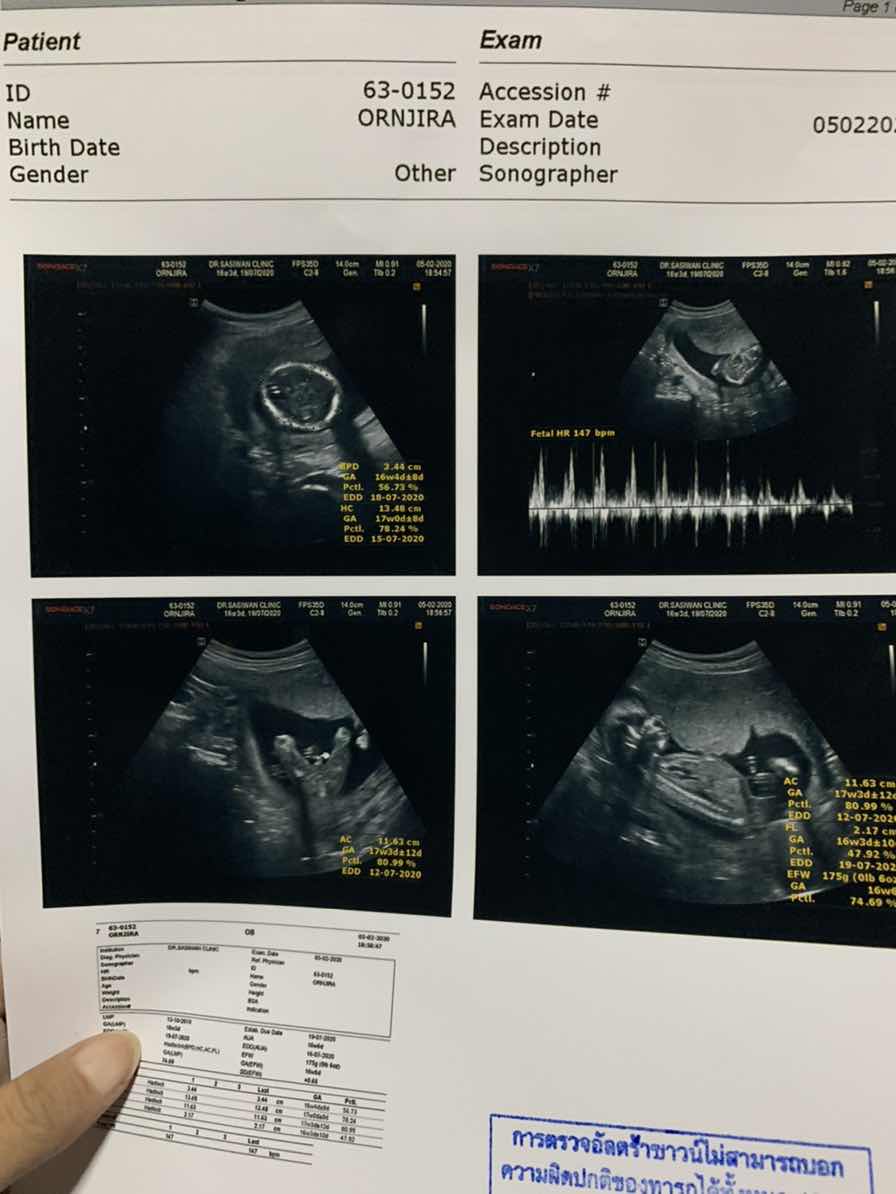

บ้านนี้ 12 ก.ค จ้า